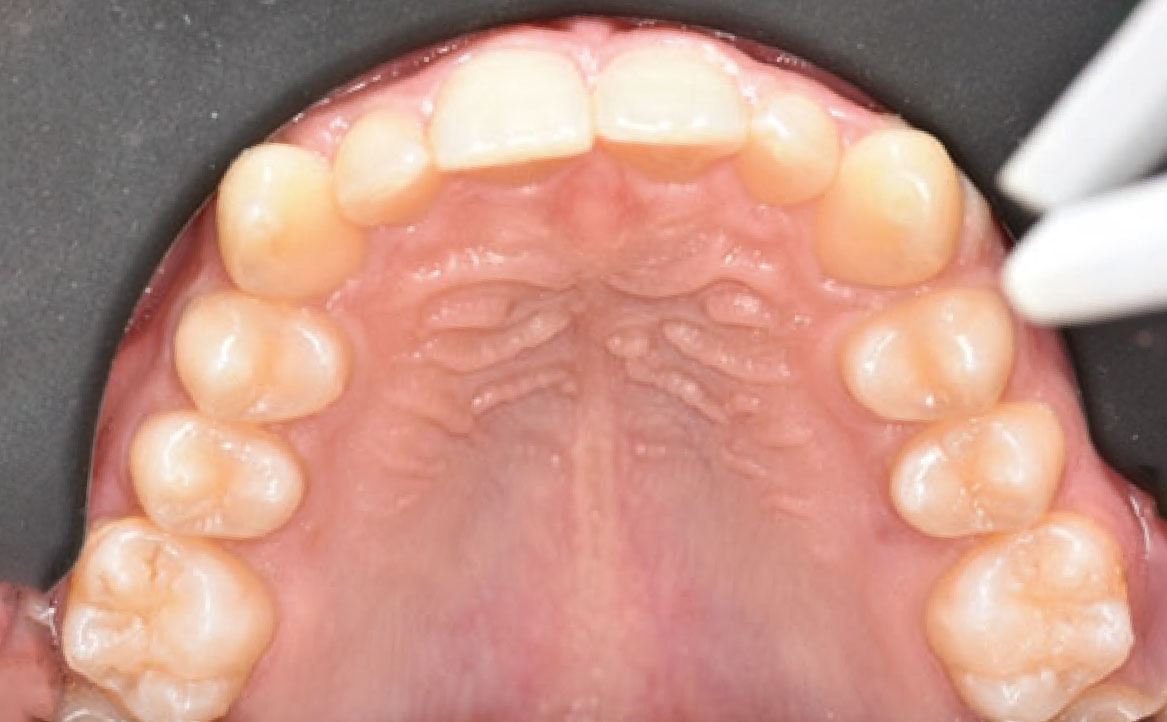

Il paziente si è presentato per la sua prima visita presso il reparto di Odontoiatria e Protesi Dentaria dell’Ospedale Vita-Salute San Raffaele diretto dal prof. E. F. Gherlone. All’esame obiettivo era evidente una malocclusione scheletrica e dentale di classe II associata a morso profondo e lieve affollamento anteriore superiore. In particolare, sono stati segnalati: rapporti occlusali di classe II, morso profondo, perdita di overjet, contrazione dell’arcata superiore e inferiore con leggero affollamento (fig. 1a-f). La richiesta del paziente era quella di migliorare l’estetica dei denti anteriori con allineatori invisibili di tipo Invisalign. Tuttavia, sia il paziente che il genitore sono stati informati che, per ragioni di efficacia e risoluzione del problema, era necessario agire anche a livello di funzionalità e risoluzione della malocclusione.

In primo luogo, sono stati prescritti entrambi gli esami radiografici ortodontici: OPT e teleradiografia latero-laterale del cranio (fig. 2a-b). Successivamente, in accordo con il genitore, è stata concordata una terapia ortodontica in due tempi. L’inizio della terapia è stato effettuato con Carriere Motion ed elastici di classe II, con l’obiettivo di migliorare la classe molare (fig. 2c-e).

Infatti, durante il primo controllo due mesi dopo, è stato osservato un miglioramento della classe molare (fig. 3a-c).